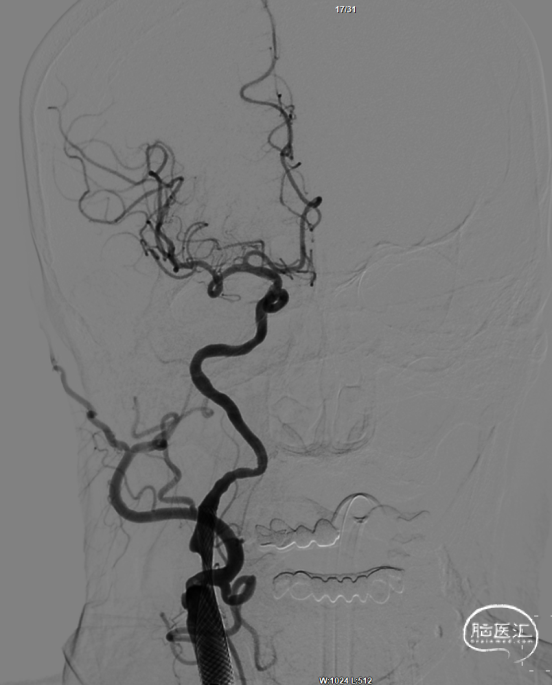

全身麻醉,右侧股动脉入路,常规行右侧颈内动脉造影,造影见右侧颈内动脉起始段重度狭窄,前向血流mTICI 2a级,远端血管床略塌陷。

将9*40mm 颈动脉支架送达目标区域,冒烟确认释放位置满意,释放支架。常规造影,血管成型满意,残余狭窄不足40%,前向血流mTICI 3级,远端血管未见缺如,收伞,伞内未见血栓。醒麻后病人清醒,安返病房。